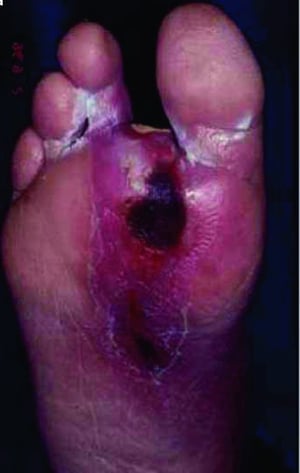

Diabetic foot complications (skin changes, ulceration, infection, gangrene) are common and are attributable to vascular disease, neuropathy, and relative immunosuppression. These complications can lead to lower extremity amputations.

Foot Ulcer

A patient with diabetes often develops microvascular disease, which may impair skin healing, so that even minor breaks in skin integrity can develop into deeper ulcers and easily become infected, particularly in the lower extremities.

© Springer Science+Business Media